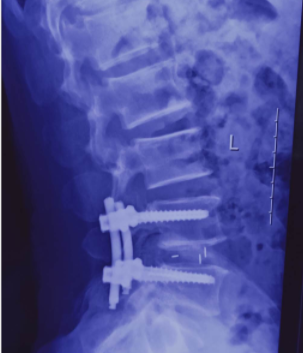

经专家会诊,决定对该患者实施微创经椎间孔入路腰椎椎体间融合术(MIS-TLIF),这也是我院首例微创经椎间孔入路腰椎椎体间融合术(MIS-TLIF)。手术过程顺利,术后患者生命体征趋于平稳、精神状态明显好转,术后3天就能拔管下地。

传统后路的椎间融合术(PLIF),术中需要腰椎两侧广泛的椎旁肌剥离,导致椎旁肌术后一定程度的失神经改变,发生纤维化,表现为腰痛、无力;需要切除两侧更多的后方结构,客观上削弱了腰椎节段的稳定性,甚至加速了邻近节段退变,术中需要对两侧的神经根进行牵拉,增加了神经根损伤的几率。微创通道下的TLIF手术避免了对椎旁肌肉进行骨膜下剥离,减轻了对椎旁软组织的损伤,保留了后方韧带复合体,出血量少,住院日短,术后并发症发生率低。